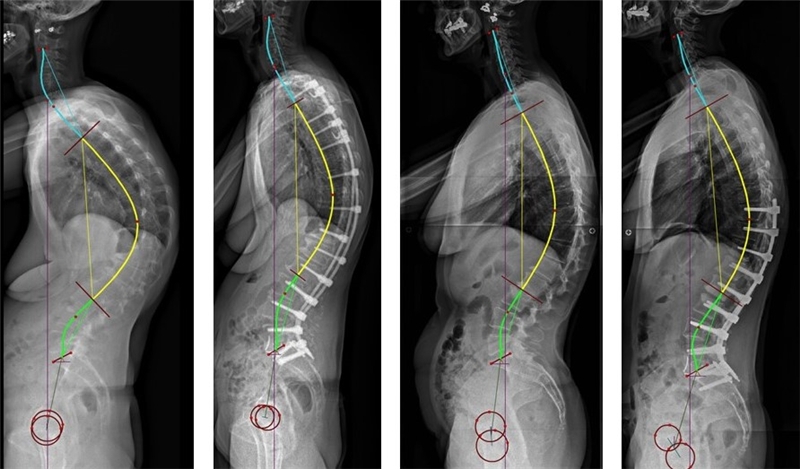

在整体后凸畸形的病例中,建议在L4行PSO截骨将矢状面序列矫正至1型或2型,此时应注意避免矫正至3型,因骨盆将发生前倾,继而导致矢状面向前失平衡

整体后凸畸形时在L4行PSO截骨将矢状面序列矫正至1型

若骨盆后倾的2型患者合并整体后凸畸形时,建议在L3或L4行较大的PSO截骨,并行长节段融合,将脊柱矫正至3型或4型。

PI较大的2型患者合并整体后凸畸形,将脊柱矫正至3型或4型